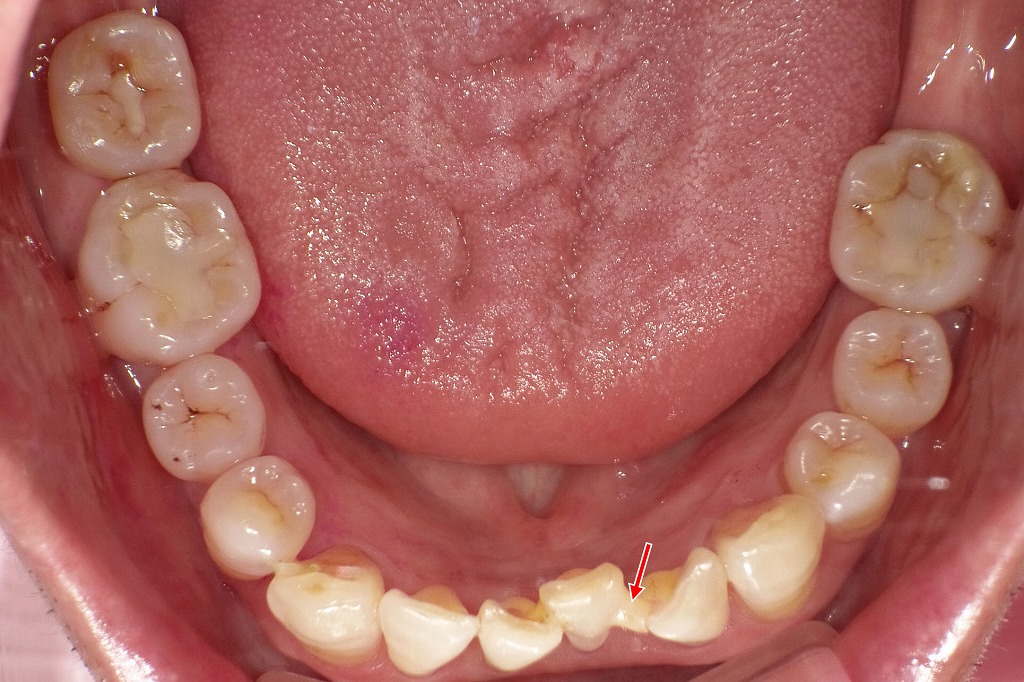

👀上下咬合面観

重度歯周病治療後の下顎咬合面観です。下顎では歯槽骨吸収は上顎に比べて比較的軽度で、全体の支持状態は保たれています。

動揺が認められた前歯部に限って、スーパーボンドを用いた暫間固定を行い(矢印部)、咬合時の安定性を確保しています。臼歯部は固定を必要としない状態で、現在は良好なプラークコントロールのもと、歯周組織は安定しています。